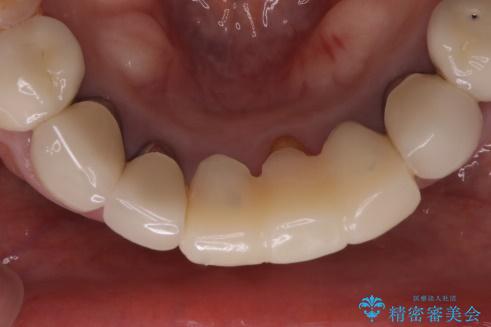

- 下の前歯のかぶせ物がが一つとれてしまい、他院で仮歯を装着されてから来院されました。

仮歯をはずし確認すると、一本の歯が土台ごとはずれて根だけになってしまって、保存が難しい状態でした。

抜歯後にブリッジを装着する計画としました。